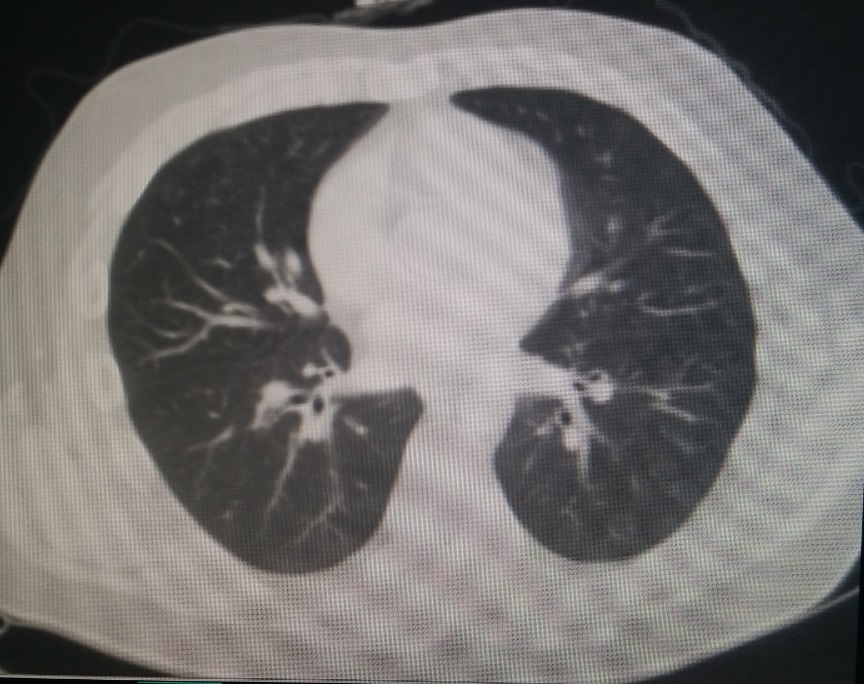

患者男,55岁,呼吸困难,气喘,查体桶状胸体症,ct如图,最可能的诊断是()

男,55岁,呼吸困难,气喘,查体桶状胸体症,ct如图,最可能的诊断是()

患者男,55岁,呼吸困难,气喘,查体桶状胸体症,ct如图,最可能的诊断是a.

男,68岁,咳嗽,气喘10年,桶状胸,ct如图,最可能的诊断为()5点击查看